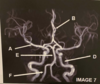

What anatomy does letter A demonstrate?

Patella

What anatomy does letter B demonstrate?

PCL

What anatomy does letter C demonstrate?

Patellar Tendon

What anatomy does letter D demonstrate?

Femoral Condyle

What anatomy does letter E demonstrate?

ACL